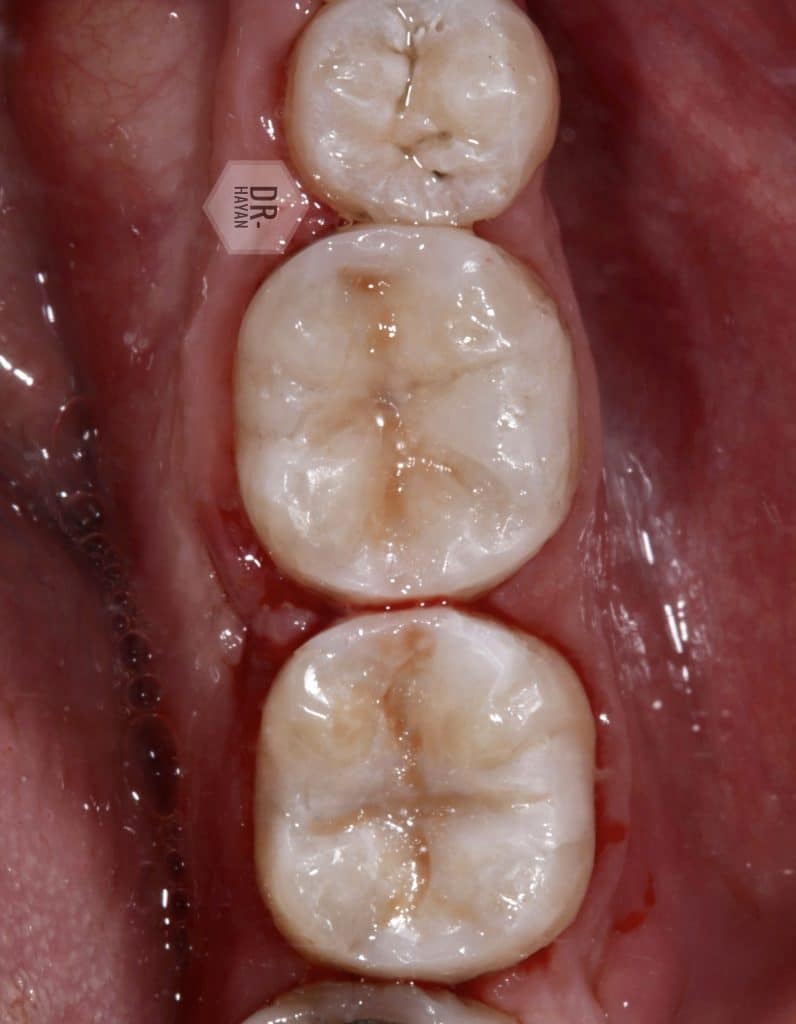

Finally, after finishing and polishing protocol